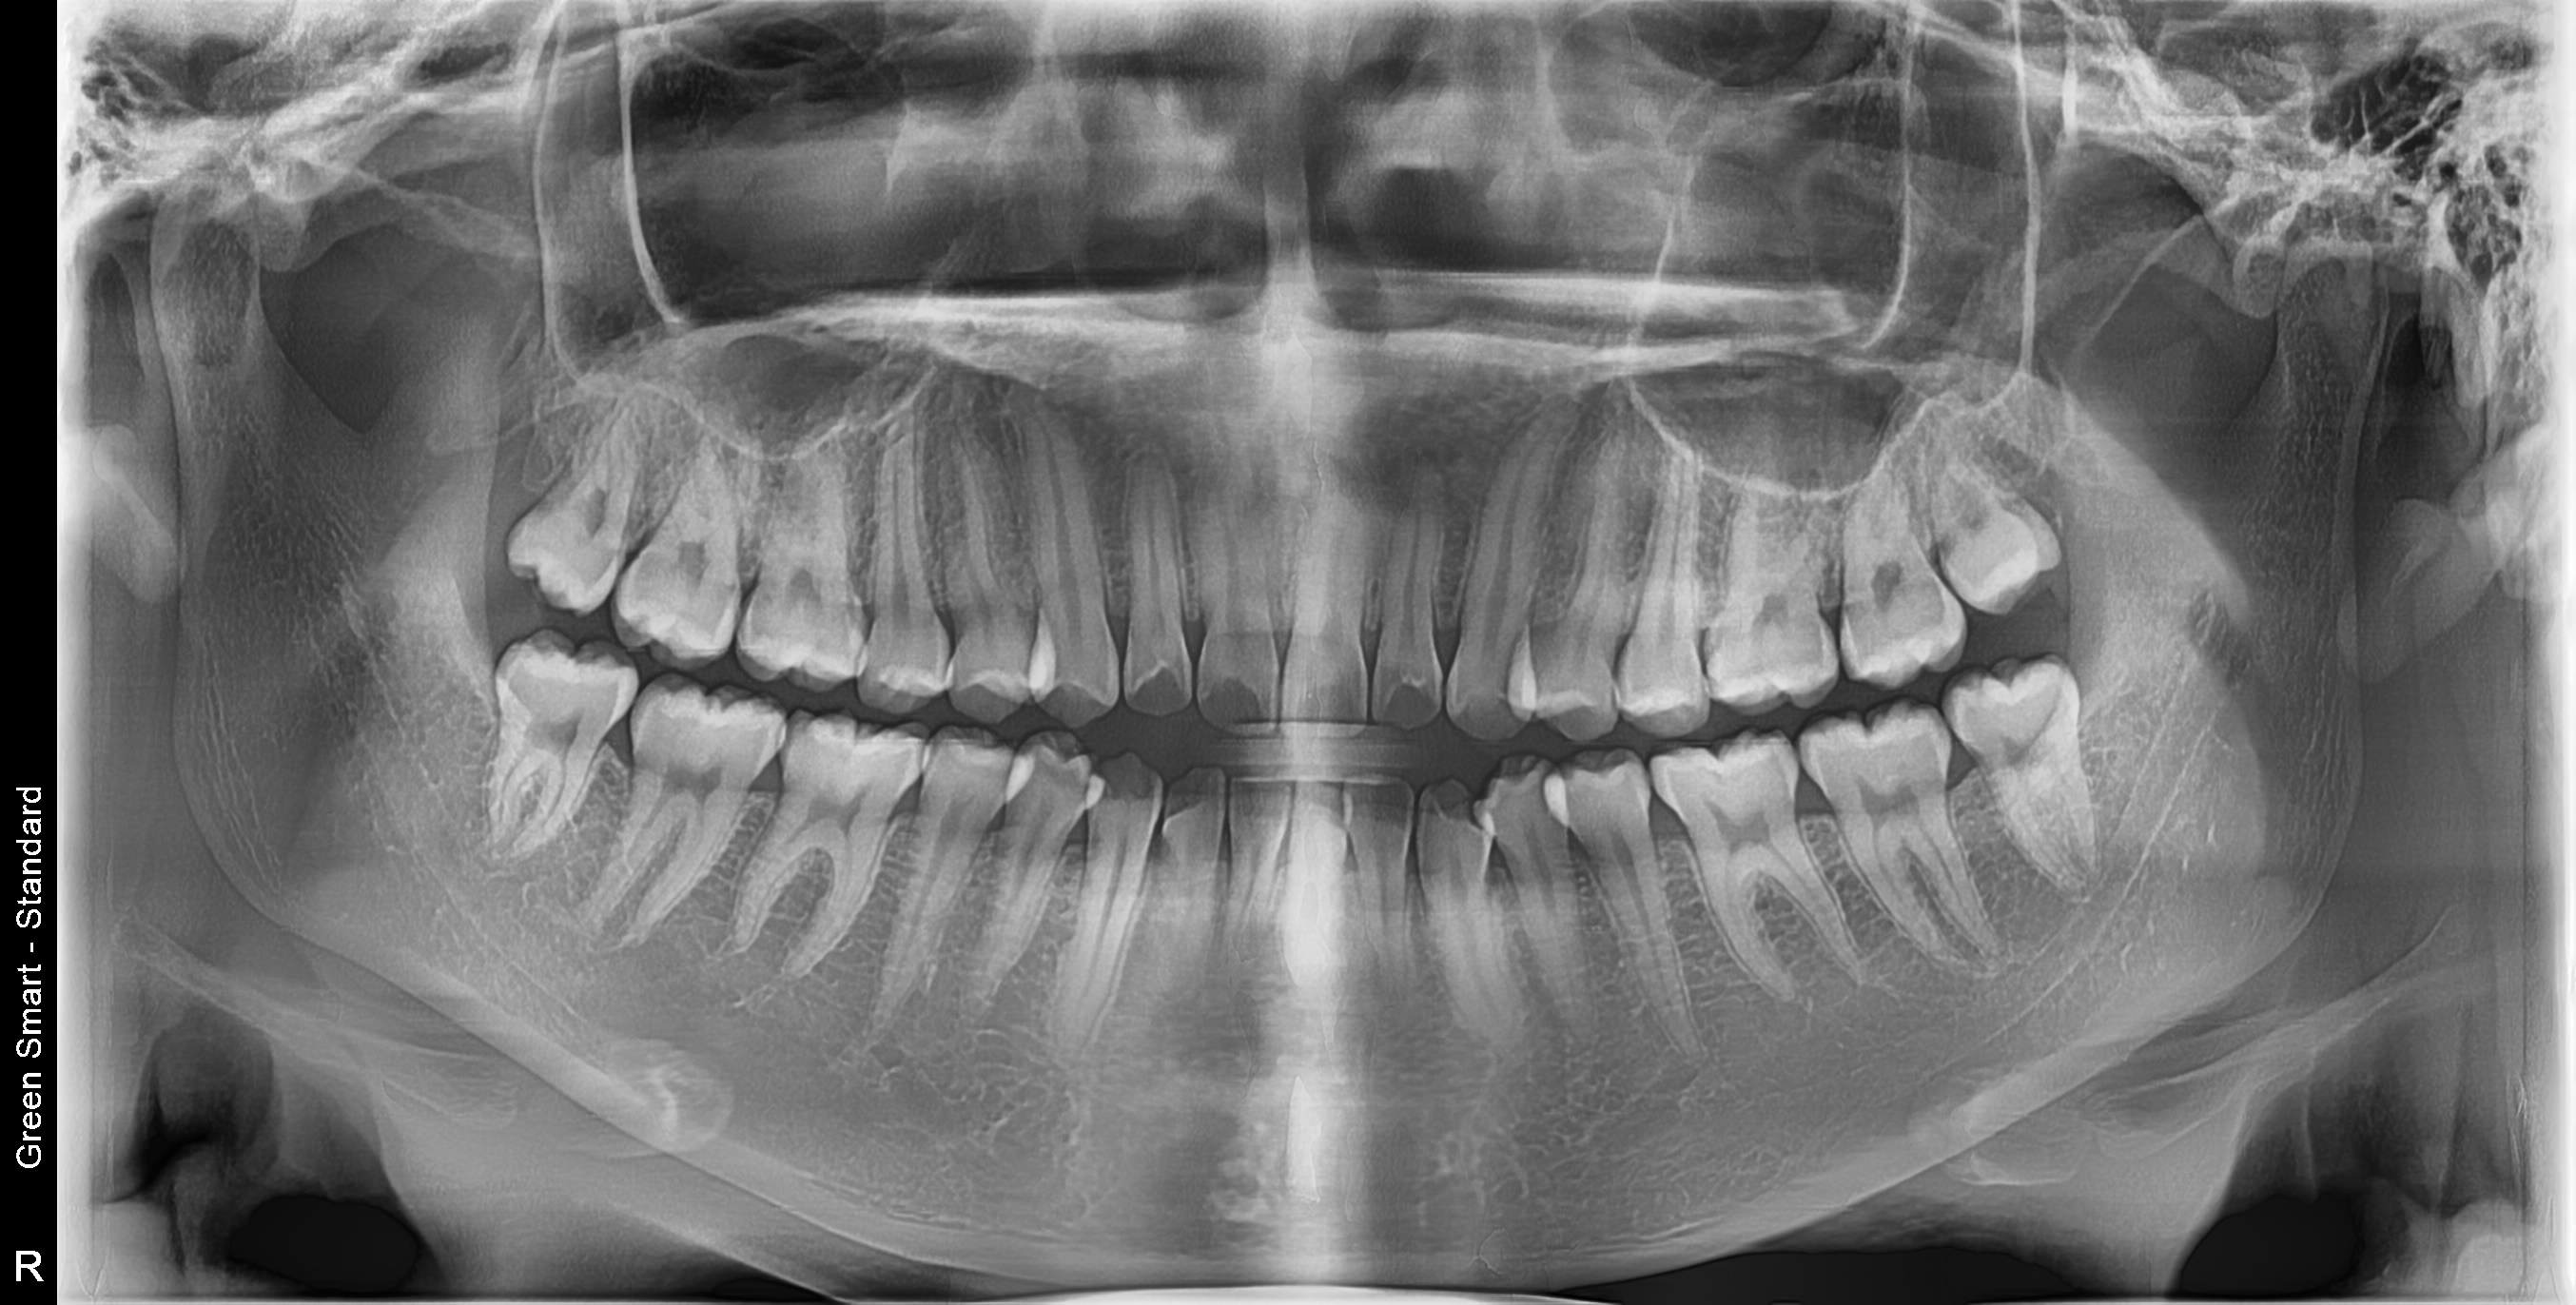

누운 사랑니

옆으로 누워 자라며 옆 치아를 압박할 수 있습니다

정상 사랑니

정상적으로 자란 사랑니도 관리가 어려워 충치 위험이 높습니다

중위험

부분매복 사랑니

음식물이 끼기 쉽고 염증이 자주 발생합니다

고위험

완전매복 사랑니

낭종 형성 가능성이 있어 조기 발치가 필요합니다

치근만곡 사랑니

뿌리가 구부러져 있어 발치 난이도가 높습니다

즉시 처치 필요

수평매복 사랑니

앞 치아를 밀어 치열 불균형과 충치를 유발합니다